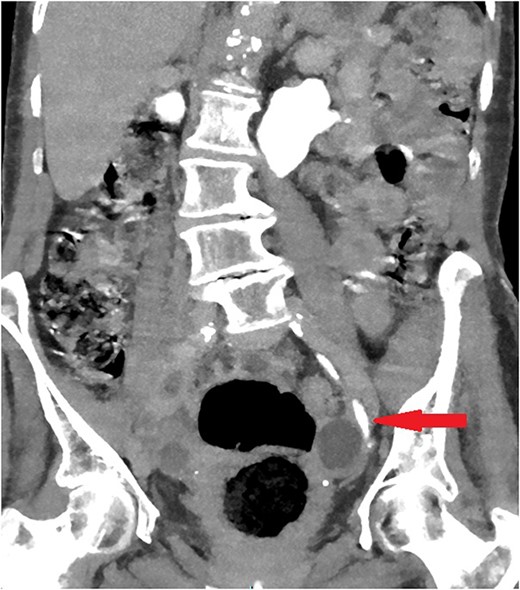

The old catheter was removed, and a replacement was inserted correctly into the bladder. The patient was managed conservatively with antibiotics. A further contrast CT was performed and showed mild extravasation of the contrast at the same level of the former catheter’s inflated balloon (Fig. 2). The patient improved clinically with conservative management, and her blood investigations remained stable. Follow-up contrast CT after 2 months was normal and showed no extravasation and no stricture (Fig. 3).

Coronal section of abdomen and pelvis contrast CT 2 weeks after the injury: Contrast flows normally without extravasation or stricture in the left ureter.